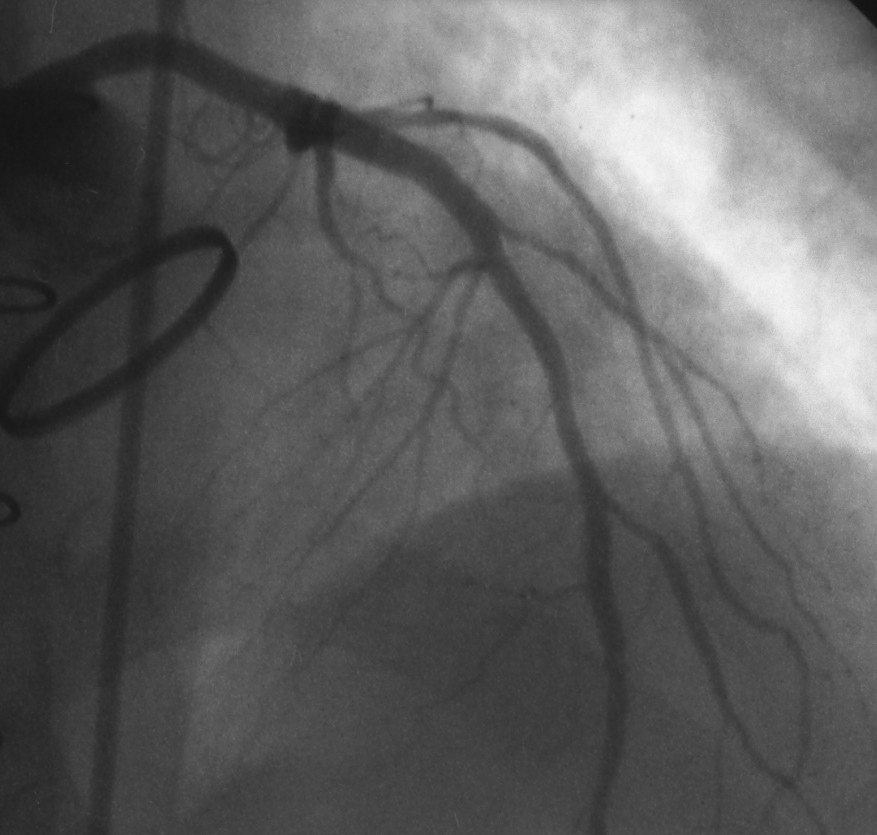

Stents to Treat Coronary Artery Blockages Cardiology JAMA The

Figure 2 from Chest pain without significant coronary stenosis after Is It Normal To Have Chest Pain After A Stent The presence of chest pain and its clinical characteristics were assessed: A stent is fitted when an. Senior cardiac nurse christopher allen says: Chest pain after pci occurs frequently even in the absence of procedural events and is considered to be due to vasospasm or coronary artery stretch. Chest pain or shortness of breath. Bleeding or swelling at the body. Is It Normal To Have Chest Pain After A Stent.